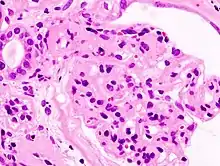

_HE.jpg.webp)